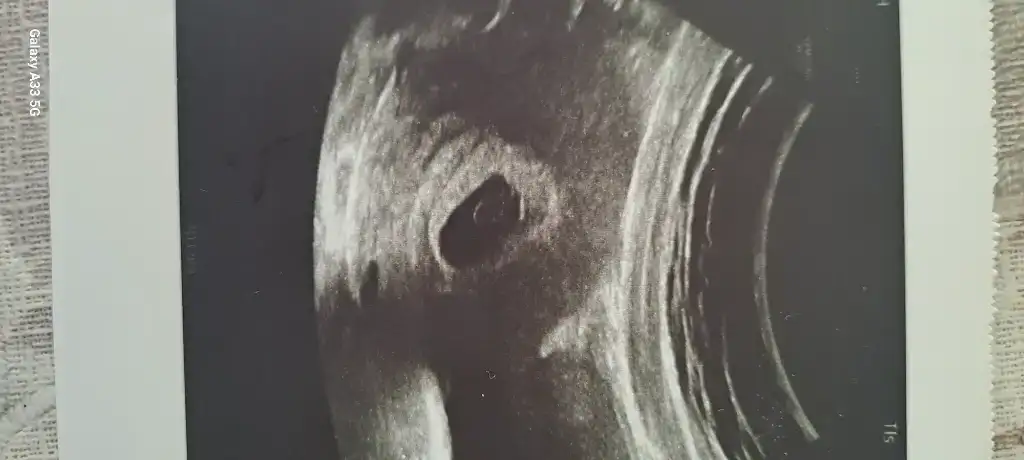

Merhaba kaç haftaliksiniz ?Bundan birsey gorebilen var mi kizlar doktor gec dollenme gibisin dedi bekleyelim yolk sac tek tas belirgin bekleyelim 1 2 hafta daha dedi ama embriyo goremedim dedi

Normalde regl tarhine gore 9 ama gec dollenme sansi ile 7 oluyoruzMerhaba kaç haftaliksiniz ?

Kaçıncı haftanda gittin canım? Ben sat a göre 6 haftalıkken gitmiştim ama geç döllenme oldugu icin 4.5haftalık frlandı muhtemelen. Embriyo yoktu benim usgmde deBundan birsey gorebilen var mi kizlar doktor gec dollenme gibisin dedi bekleyelim yolk sac tek tas belirgin bekleyelim 1 2 hafta daha dedi ama embriyo goremedim dedi

Bugun gittim gec dollenme ye gore 7 hafta gibiyiz bugunKaçıncı haftanda gittin canım? Ben sat a göre 6 haftalıkken gitmiştim ama geç döllenme oldugu icin 4.5haftalık frlandı muhtemelen. Embriyo yoktu benim usgmde de

Karından bakildiysa belki ondan görülmemiştir inşallah 2 hafta sonra bebesi de kalbini de görürsünüzNormalde regl tarhine gore 9 ama gec dollenme sansi ile 7 oluyoruz

Karindan ilk defa yolk sac tektas goruldu o bile bi umut oldu bizim icin doktor da umitlendi 1 2 hafta bekle dedi hayirlisi insallahKarından bakildiysa belki ondan görülmemiştir inşallah 2 hafta sonra bebesi de kalbini de görürsünüz

İnşallah güzel haberler alacaksınız burda hep beraber sevinecegizKarindan ilk defa yolk sac tektas goruldu o bile bi umut oldu bizim icin doktor da umitlendi 1 2 hafta bekle dedi hayirlisi insallah

duydunuz mu kalp atışını bugunBugun gittim gec dollenme ye gore 7 hafta gibiyiz bugun

YOk daha bebis goremedik ki biz canimduydunuz mu kalp atışını bugun